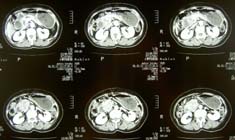

ヘリカルCT連続画像 |